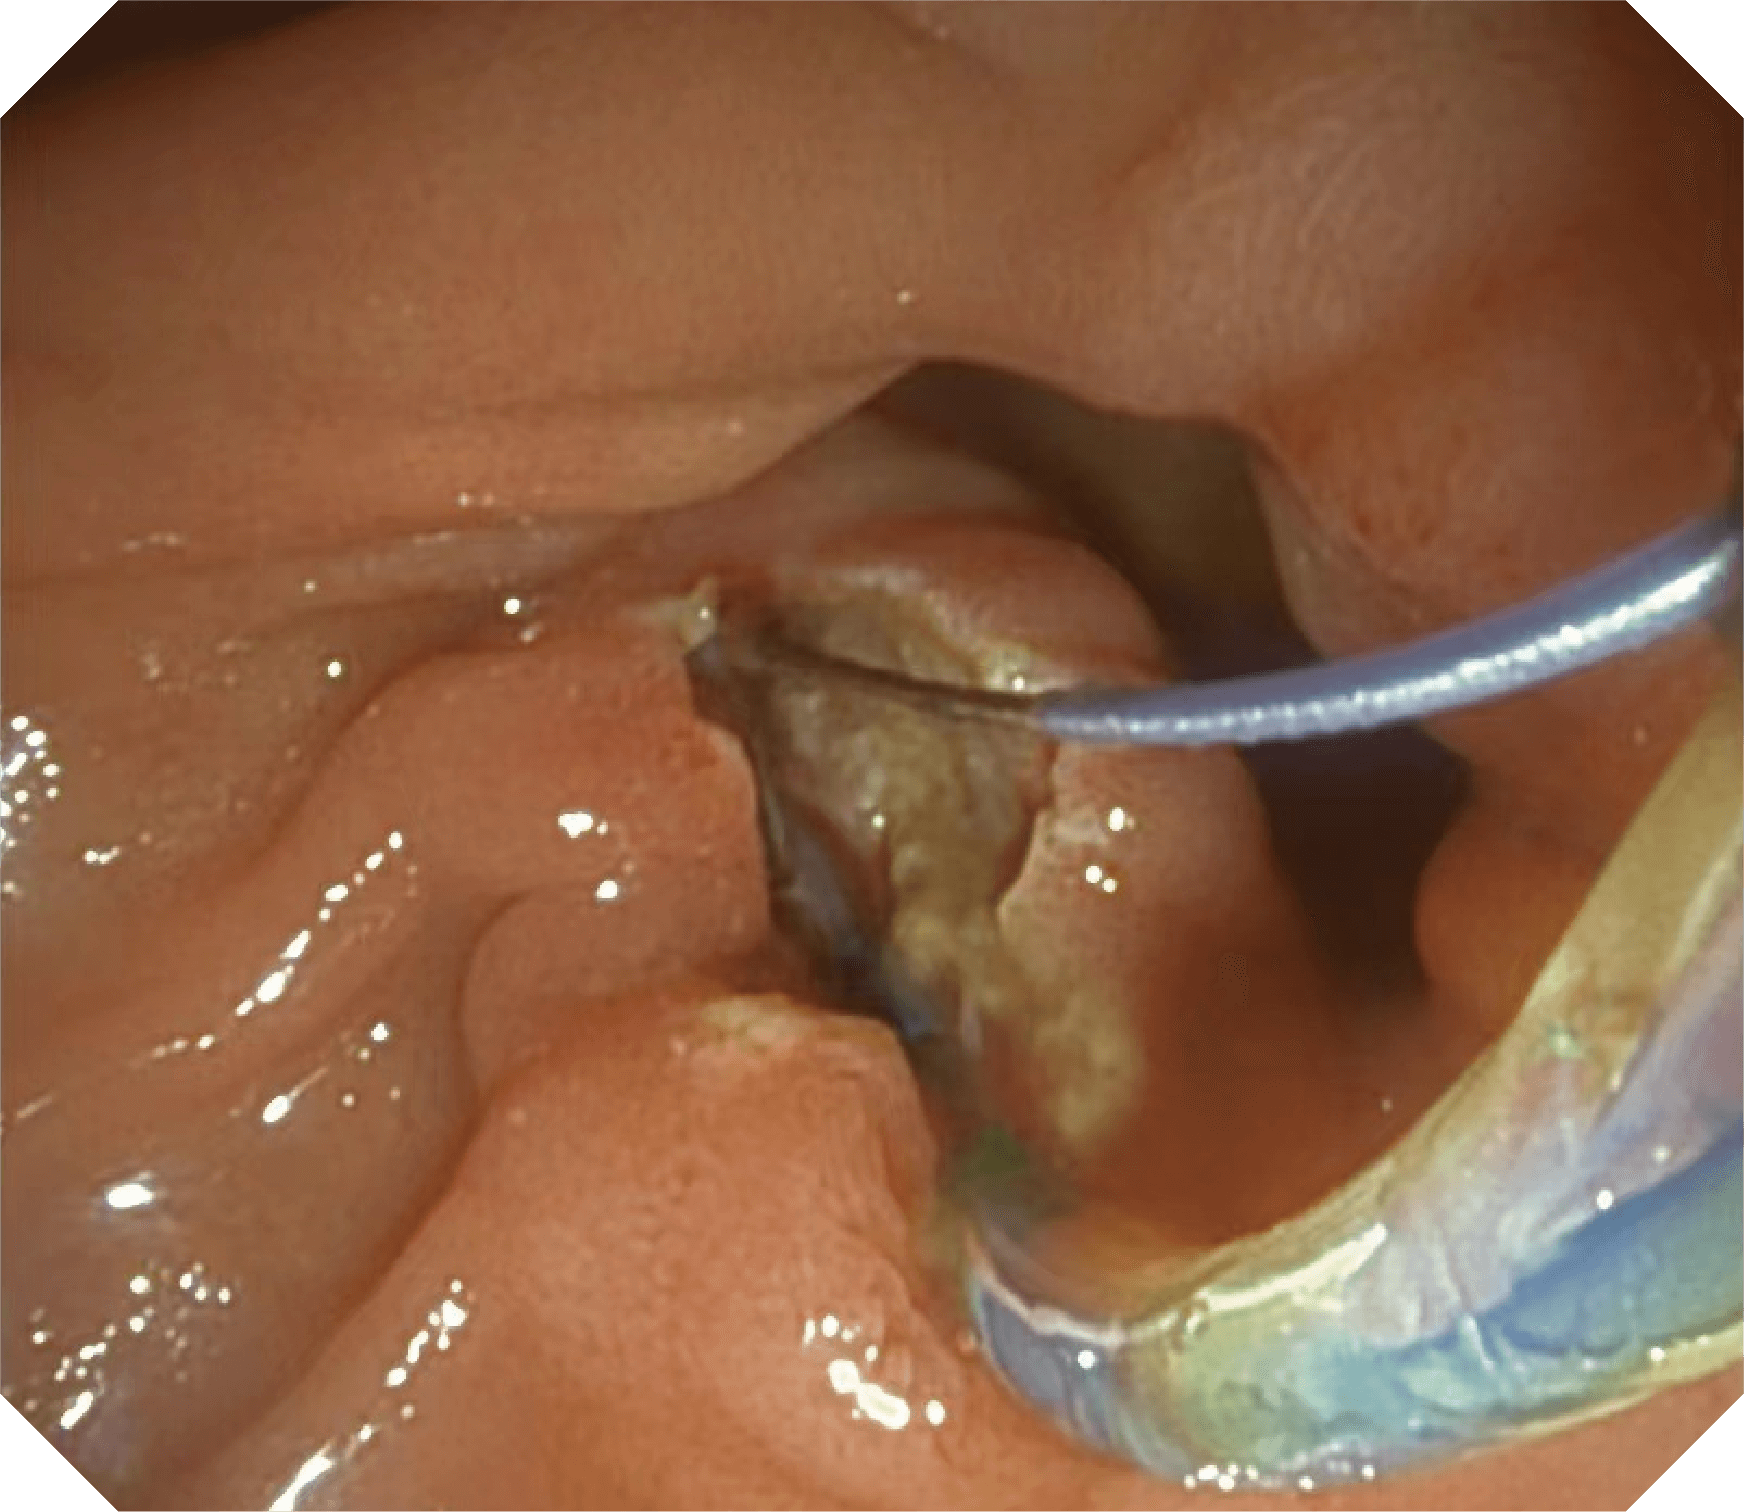

4.2mm大钳道,器械交换更顺畅

导丝机械锁紧功能

V槽设计提升导丝控制

更好的通过性,更稳定的镜体支撑力